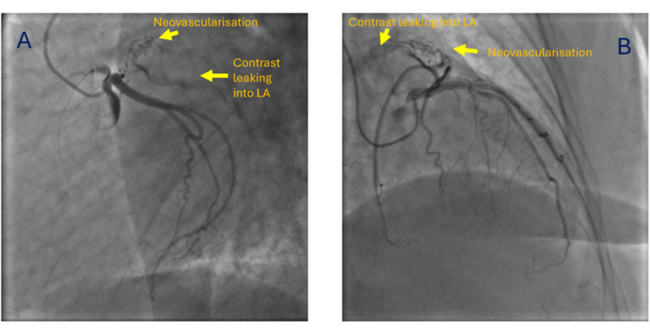

She was taken up for a preoperative coronary angiography with a plan for a subsequent mechanical mitral valve replacement. The coronary angiogram revealed normal epicardial coronary arteries. However, the atrial branch of the left circumflex artery was seen giving small branches to a left atrial appendage (LAA) clot (neovascularization), with contrast leaking into the left atrium (LA) from these neovessels (Figure, Video). A transesophageal echocardiogram later confirmed the LAA clot. The patient was subsequently planned for a mechanical mitral valve replacement and LAA clot removal.

In a previous study from our center, which included 81 patients with rheumatic mitral stenosis, angiography predicted thrombosis by demonstrating neovascularity, manifesting as a bunch of small vessels arising from the circumflex branch of the left coronary artery and terminating in a network of smaller vascular channels, with a blush of contrast medium consolidating into small lakes.1 For recognizing thrombi in the LA or LAA, selective left coronary angiogram demonstrated sensitivity and specificity of 72.7% and 92.7%, respectively, and an 88.8% predictive value.1